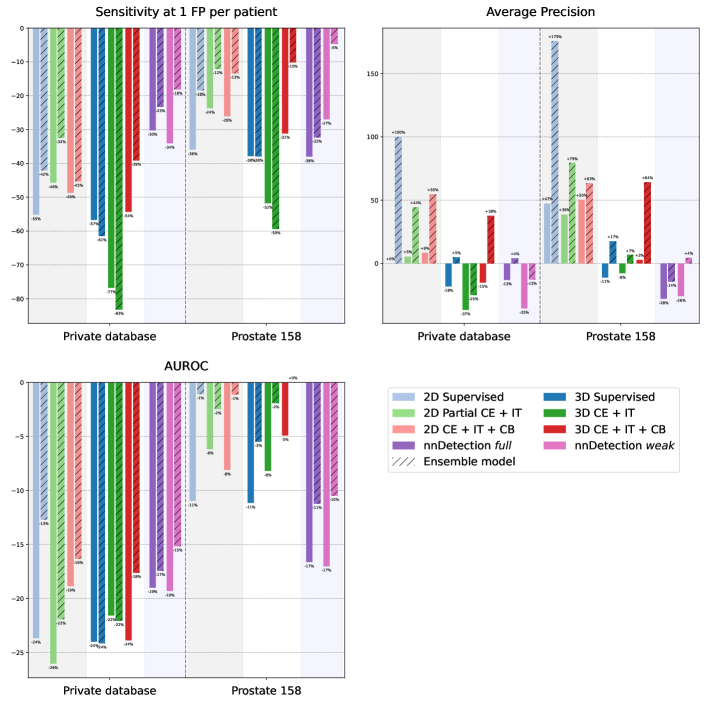

Figure 2 shows the relative performance of the models on the two test datasets, that is Prostate158 and our private database, compared to the performance of the same model evaluated on the in-distribution validation dataset. We did not report the results for the cases where the models are trained with partial and negative cross entropies as their absolute performances are much lower than the others.

For most of the metrics and models, there is, as one could have expected, a notable drop in performances when the models are evaluated on a test set that has been acquired in a different setup from that of the training dataset. The average performance decrease ratio is of 28% among all models and metrics. This can reach values as low as -61% for supervised models. Quite surprisingly, the Average-Precision score is even or better – sometimes by a large amount – on the test datasets than on the validation datasets for many models.

Compared to fully supervised models, the weak models trained with CB constraint loss has a more favorable relative change in 19 configurations out of 24 (6 configurations correspond to the PI-CAI dataset and are thus not considered here). This advantage is also found when compared to the models trained with the IT loss. Ensemble predictions, with a rule as simple as averaging the output probability maps of models obtained from several trainings, almost always help reducing the performance gap in generalization.

Among all compared methods, the weak model with CB loss is the most robust to unseen data domains. As seen on Figure 2, it indeed suffers the least from a performance drop when tested on data that do not belong to the training distribution.